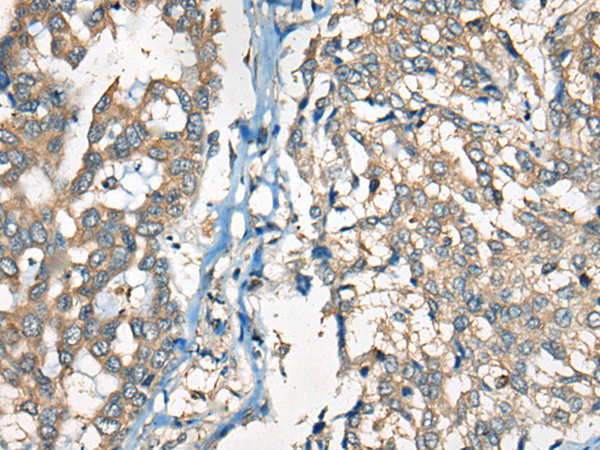

IHC positive control: |

Human liver cancer |